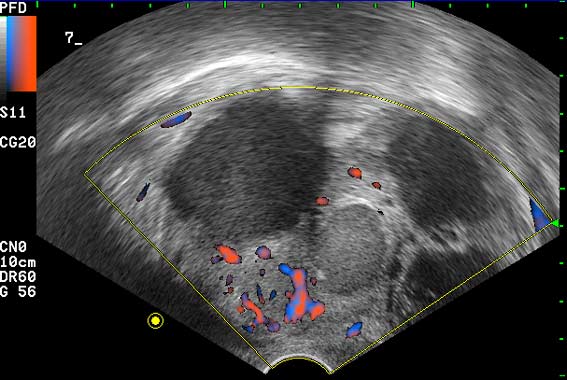

ТВУЗИ: гнойный аднексит. Adnexitis, ultrasonography.

Трансвагинальное УЗИ органов малого тазау женщины 37 лет с высокой температурой и симптомами интоксикации.